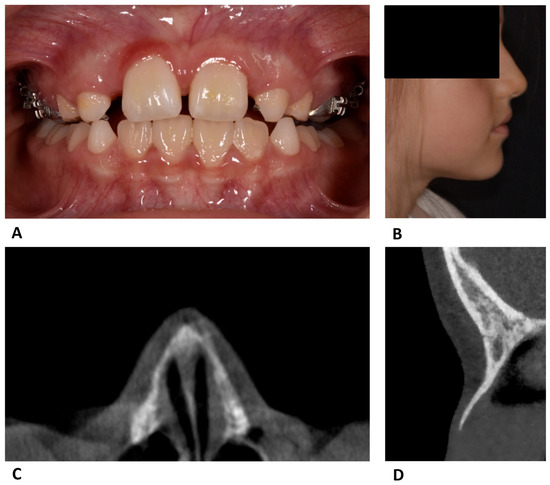

Nasal Fracture During Maxillary Expansion—A Rare Complication?

by Katharina Obermeier, Wenko Smolka, Philipp Poxleitner, Natasa Puskar and Hisham Sabbagh

Reports 2026, 9(2), 108; https://doi.org/10.3390/reports9020108 - 1 Apr 2026

Background and Clinical Significance: This case report describes an unusual complication in an 8-year-old female patient undergoing ME (maxillary expansion) with a tooth-supported maxillary expander with the hyrax screw. Case presentation: After the 36th screw turn in the 5th week of treatment, the [...] Read more.

Background and Clinical Significance: This case report describes an unusual complication in an 8-year-old female patient undergoing ME (maxillary expansion) with a tooth-supported maxillary expander with the hyrax screw. Case presentation: After the 36th screw turn in the 5th week of treatment, the patient reported pressure and pain symptoms and the patient’s parents observed a bone elevation at the bridge of the nose. The patient was referred to for clinical examination which revealed a bilateral infraorbital hematoma and a movable, and highly sensitive, nasal area upon palpation. A cone-beam computed tomography (CBCT) scan confirmed a displaced nasal bone fracture. Conservative treatment was immediately initiated by reversing the hyrax screw four times, followed by ten additional turns over the next 7 days for a total of 14 back-turns. This procedure led to an immediate improvement in symptoms. An 8-week follow-up CBCT confirmed the physiological repositioning of the nasal bones and healing of the fracture. Conclusions: Although nasal bone fracture is a rare complication of ME, particularly in children, clinicians should be aware of this potential risk and remain vigilant for symptoms of high pressure and pain in the orbito-nasal area. If a nasal fracture is suspected during orthodontic treatment, the orthodontist should immediately cease screw activation. In selected cases, careful reversal of the screw, as described in this report, may be considered as a conservative treatment. Full article